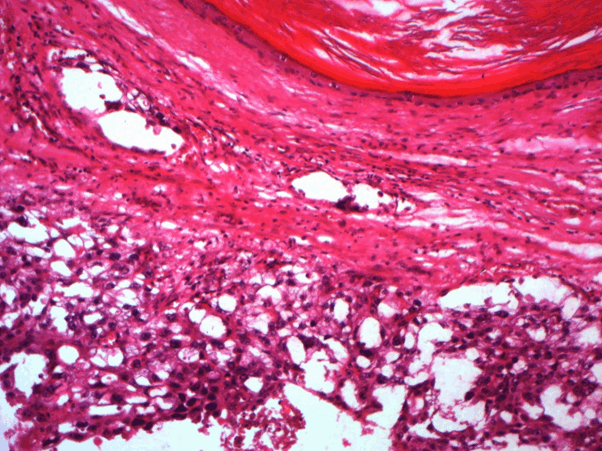

A 28-year-old patient smoking with 10 packets / year was referred to internal medicine for suspicion of Langerhans's histiocytosis. The patient was hospitalized in March 2013, at the Urology Department, for a painful left inguinal swelling. Testicular ultrasound showed an atrophic right testicle in place with epididymis of normal appearance. The left testis is of inguinal seat with pseudo-nodular heterogeneous hypertrophied aspect and a fuzzy limits containing areas of necrosis and calcifications. The left epididymis is thickened heterogeneous and contains calcifications. This echographic pattern was quite suggestive of a malignancy. The serum determination of tumor markers was within normal: a level of LDH at 220 U / l (<1, 5XN), an α feto -protein level at 85 ng / ml (<100ng/ml) and beta HCG at 5ng / ml (<5000ng/ml). The patient had a left orchi - epididymectomy. The histopathological examination of the surgical specimen found a sub capsular mixed germinal tumor of the testicle with extensive necrotic foci and without epididymal infiltration. (Figure 1)

Figure 1. Teratoma component of germinal cell tumor (HEx400)